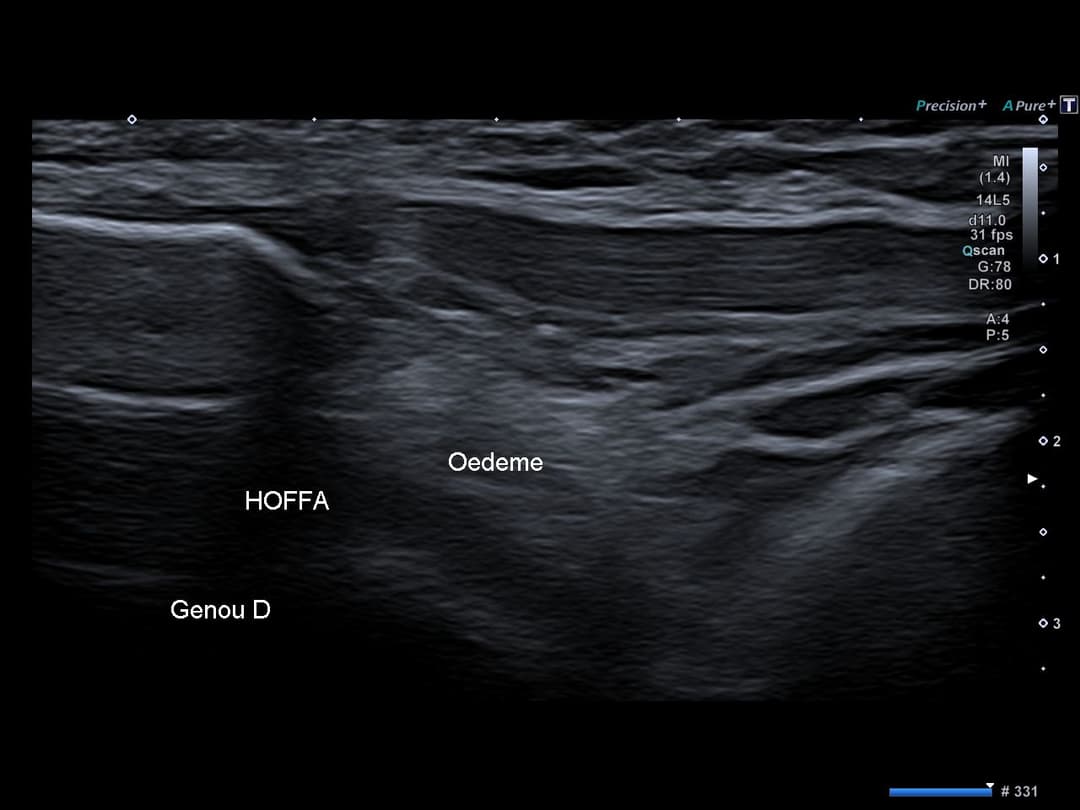

Accentuation hyperéchogène dans la graisse de Hoffa plutôt dans son compartiment latéral, traduisant un oedeme ou un remaniement fibreux.